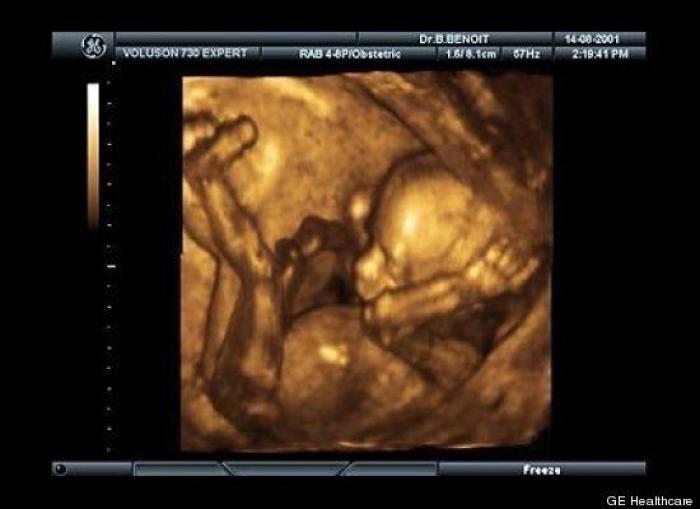

En esta galería puedes ver en fotos como es el desarrollo de un feto de semana en semana:

Desarrollo del feto, en fotos

Ver la galería